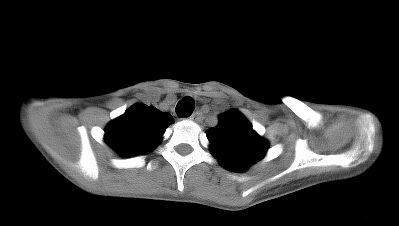

标题: CT22395:左侧肱骨头占位性病灶。 [打印本页]

标题: CT22395:左侧肱骨头占位性病灶。

这是一个17岁的花季少女,在上学期间,自觉左侧肩部不适,家人误以为是外伤引起,没有重视,近日疼痛加剧,来院就诊,ct检查发现如下.

诊断依据:1、骨质破坏,软组织肿胀。2、从纵隔窗上看,这么年轻就有纵隔淋巴结钙化,提示有可能有肺结核病史,这是诊断左肩关节结核的又一重大证据,建议结合病史并提供肺窗。

骨质膨胀性破坏,软组织肿胀,有新骨形成。考虑骨肉瘤